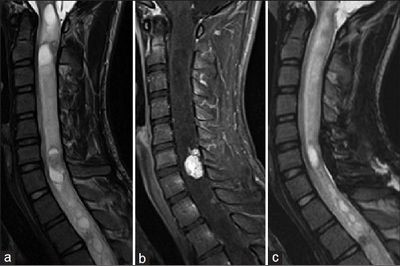

Первое что необходимо сделать это пройти МРТ поясничного отдела позвоночника. Там мы увидим грыжу (протрузию) диска которую вы себе заработали, используя свой позвоночник в качестве подъёмного крана. Второе #8212; вам необходимо ответить на следующие вопросы, есть, или нет у вас: язвы желудка, или 12-перстной кишки, астмы, гипертонии, диабета, болезней печени и почек, аллергии на мед. препараты.

МРТ необходимо сделать в обязательно порядке. Пока вы не посетите врача в поликлинике, для облегчения боли, следует поделать три дня инъекции: дексаметазон 4 мг. #8212; 1 мл. внутримышечно и кетонал 5% #8212; 2 мл. внутримышечно. Также параллельно уколам принимаем мидокалм по 150 мг три раза в день. После уколов может (не обязательно, но вероятность есть) подниматься давление. На всякий случай проконтролируйте этот момент.